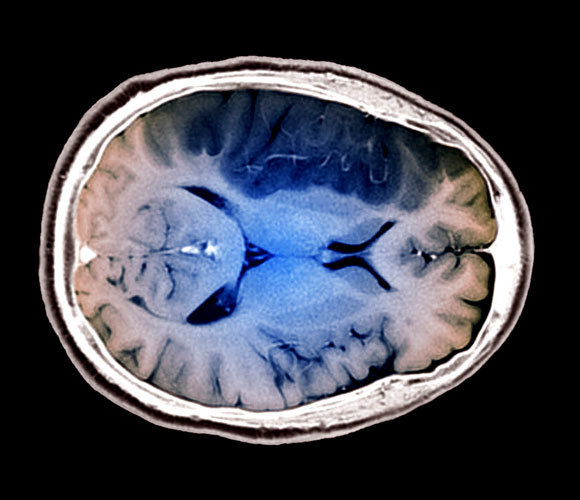

סריקת MRI של מוח לאחר שבץ. עם זאת, החוקרים מצאו רק מִתאם, לא קשר סיבתי | צילום: Science Photo Library

במאמר הנוכחי הפרידו החוקרים את הנתונים על משתתפי המחקר האירופי לשלוש קבוצות: אוכלי בשר, אוכלי דגים וצמחונים, ובחנו את הסיכון של חברי כל קבוצה לחלות במחלות לב או לעבור שבץ מוחי. נמצא כי הסיכון של אוכלי דגים או צמחונים לחלות במחלת לב היה נמוך ב-13 אחוז ו-22 אחוז בהתאמה לעומת אוכלי בשר. בנוסף נמצא כי הסבירות שצמחוני יחווה שבץ מוחי גבוהה ב-20 אחוז מהסבירות שחברי שתי הקבוצות האחרות יחוו שבץ. הסכנה היא בעיקר של שבץ המורגי, שנגרם מקרע בכלי דם במוח.